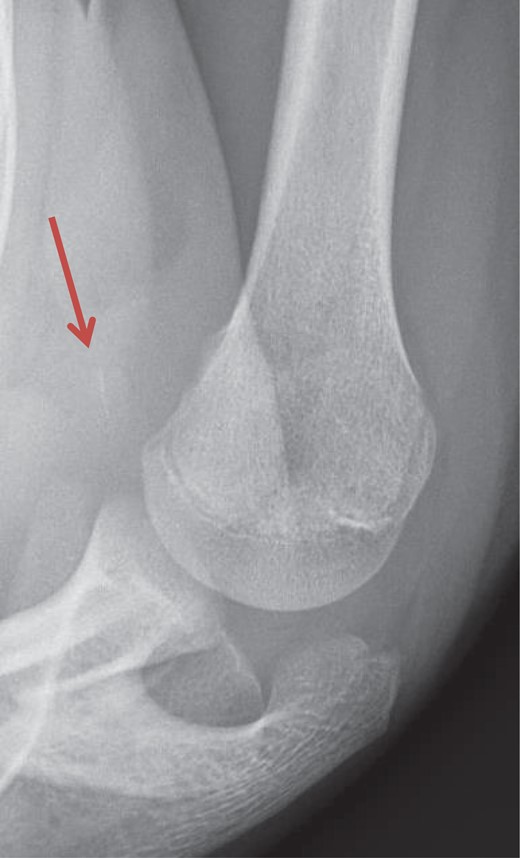

Axillary lateral view of the injured right shoulder. The avulsion fragment of the lesser tuberosity is marked by the red arrow.